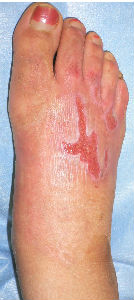

45) 20代か30代の女性の足背熱傷。S大学病院形成外科で治療を受け,「皮膚移植しないと治らない」と説明を受け手術予定だったが,すんでのところでS大学病院を逃げ出して受診,救出(?)した。プラスモイスト貼付のみで完治。運動障害なし。